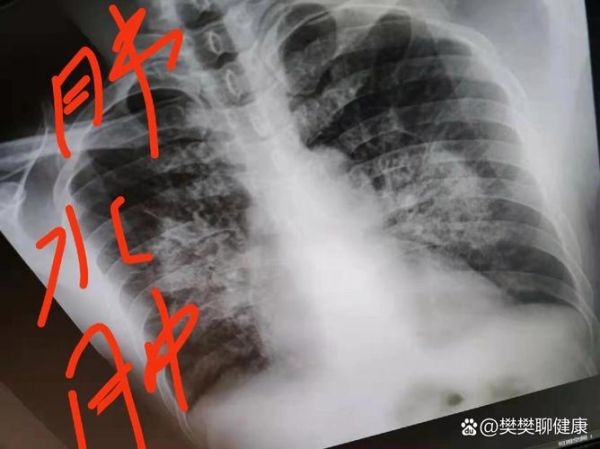

高原肺水肿(High Altitude Pulmonary Edema,HAPE)是高海拔地区最常见、最凶险的急性高原病。它发生在快速上升到海拔2500米以上的人群中,由于低氧刺激导致肺血管异常收缩,肺毛细血管压力骤升,血浆与红细胞大量渗入肺泡,最终肺泡被液体淹没,氧气无法弥散入血。

2023年10月,一名28岁男性从成都直飞稻城(海拔4410米),当晚出现干咳,次日晨咳粉红色痰,血氧58%。因交通延误,直至发病第20小时才乘直升机降至2600米,途中发生室颤,抢救无效死亡。尸检显示双肺重量达正常3倍,肺泡腔完全被水肿液及红细胞填充。